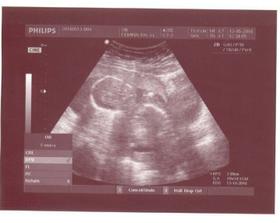

15.3.2010 - ďalšie poradňa....taaakže poradňu máme za sebou...vyčakala som sa na doktorku hodinu a pol lebo musela ísť spraviť nejaké zákroky...potom ked prišla sme pozerali bábätko a bolo to niečo nádherné....prvýkrát som videla ako sa malé pohlo, bol to super zážitok...pohlavie sme sa síce nedozvedeli, ale nevadí, hádam nabudúce....

7.6.2010 - ďalšia poradňa, a budú ževraj aj glukózové testy.... takže poradna sa musela preložiť na 10.6. a dopadla až super, dozvedeli sme sa že čakáme chlapčeka a tak sme šťastní a hned sme si potom v TESCU spravili radosť a kupili 4 ks dupačiek :o))